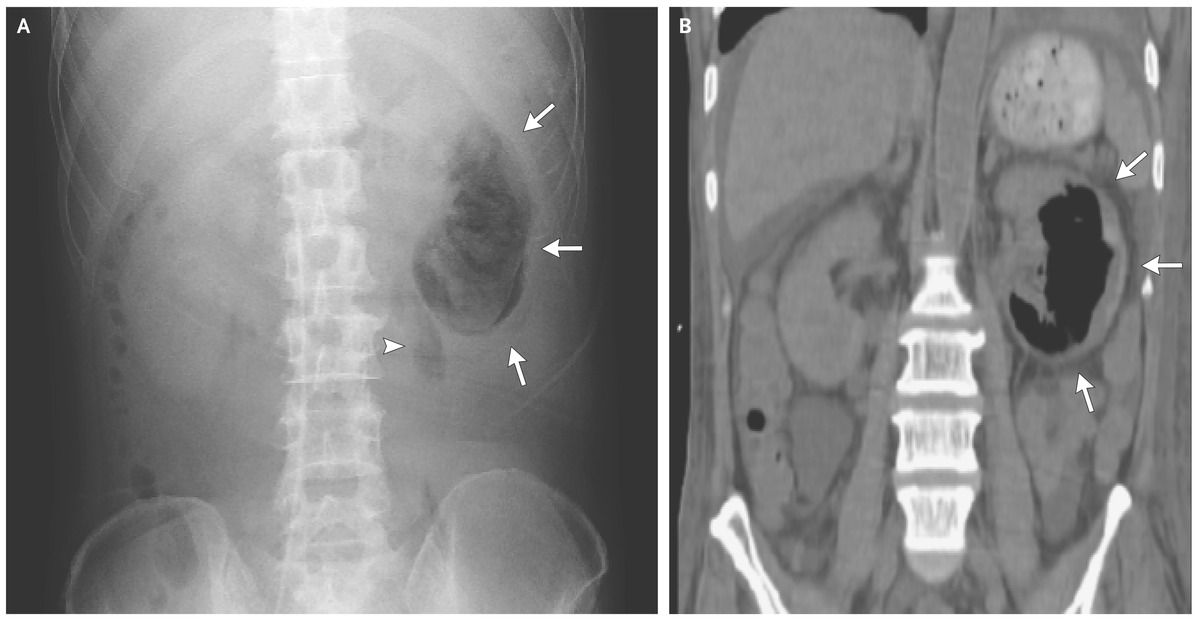

Abdominal radiography (Panel A) and computed tomography (Panel B) revealed gas collection in the parenchyma (arrows) and perinephric space (arrowhead) of the left kidney.

The patient received a diagnosis of emphysematous pyelonephritis, possibly caused by retrograde infection related to diabetes-associated neurogenic bladder.